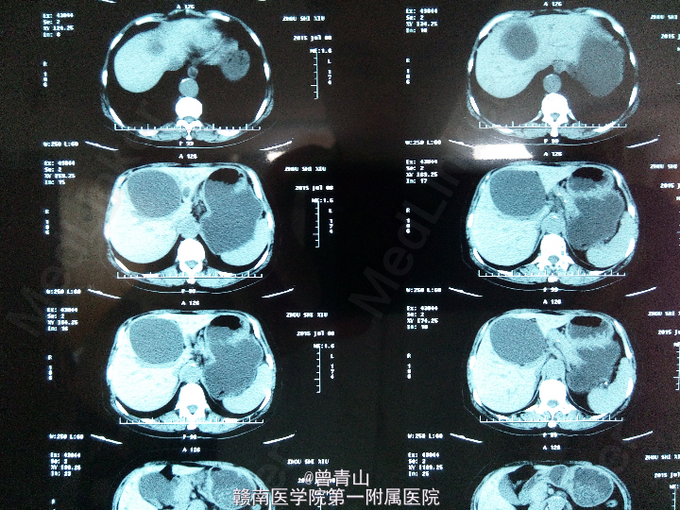

查体无异常。腹部彩超示:肝囊肿87×66mm。腹部增强CT提示肝囊肿。

诊断为肝囊肿。在全麻下行腹腔镜下囊肿开窗术。